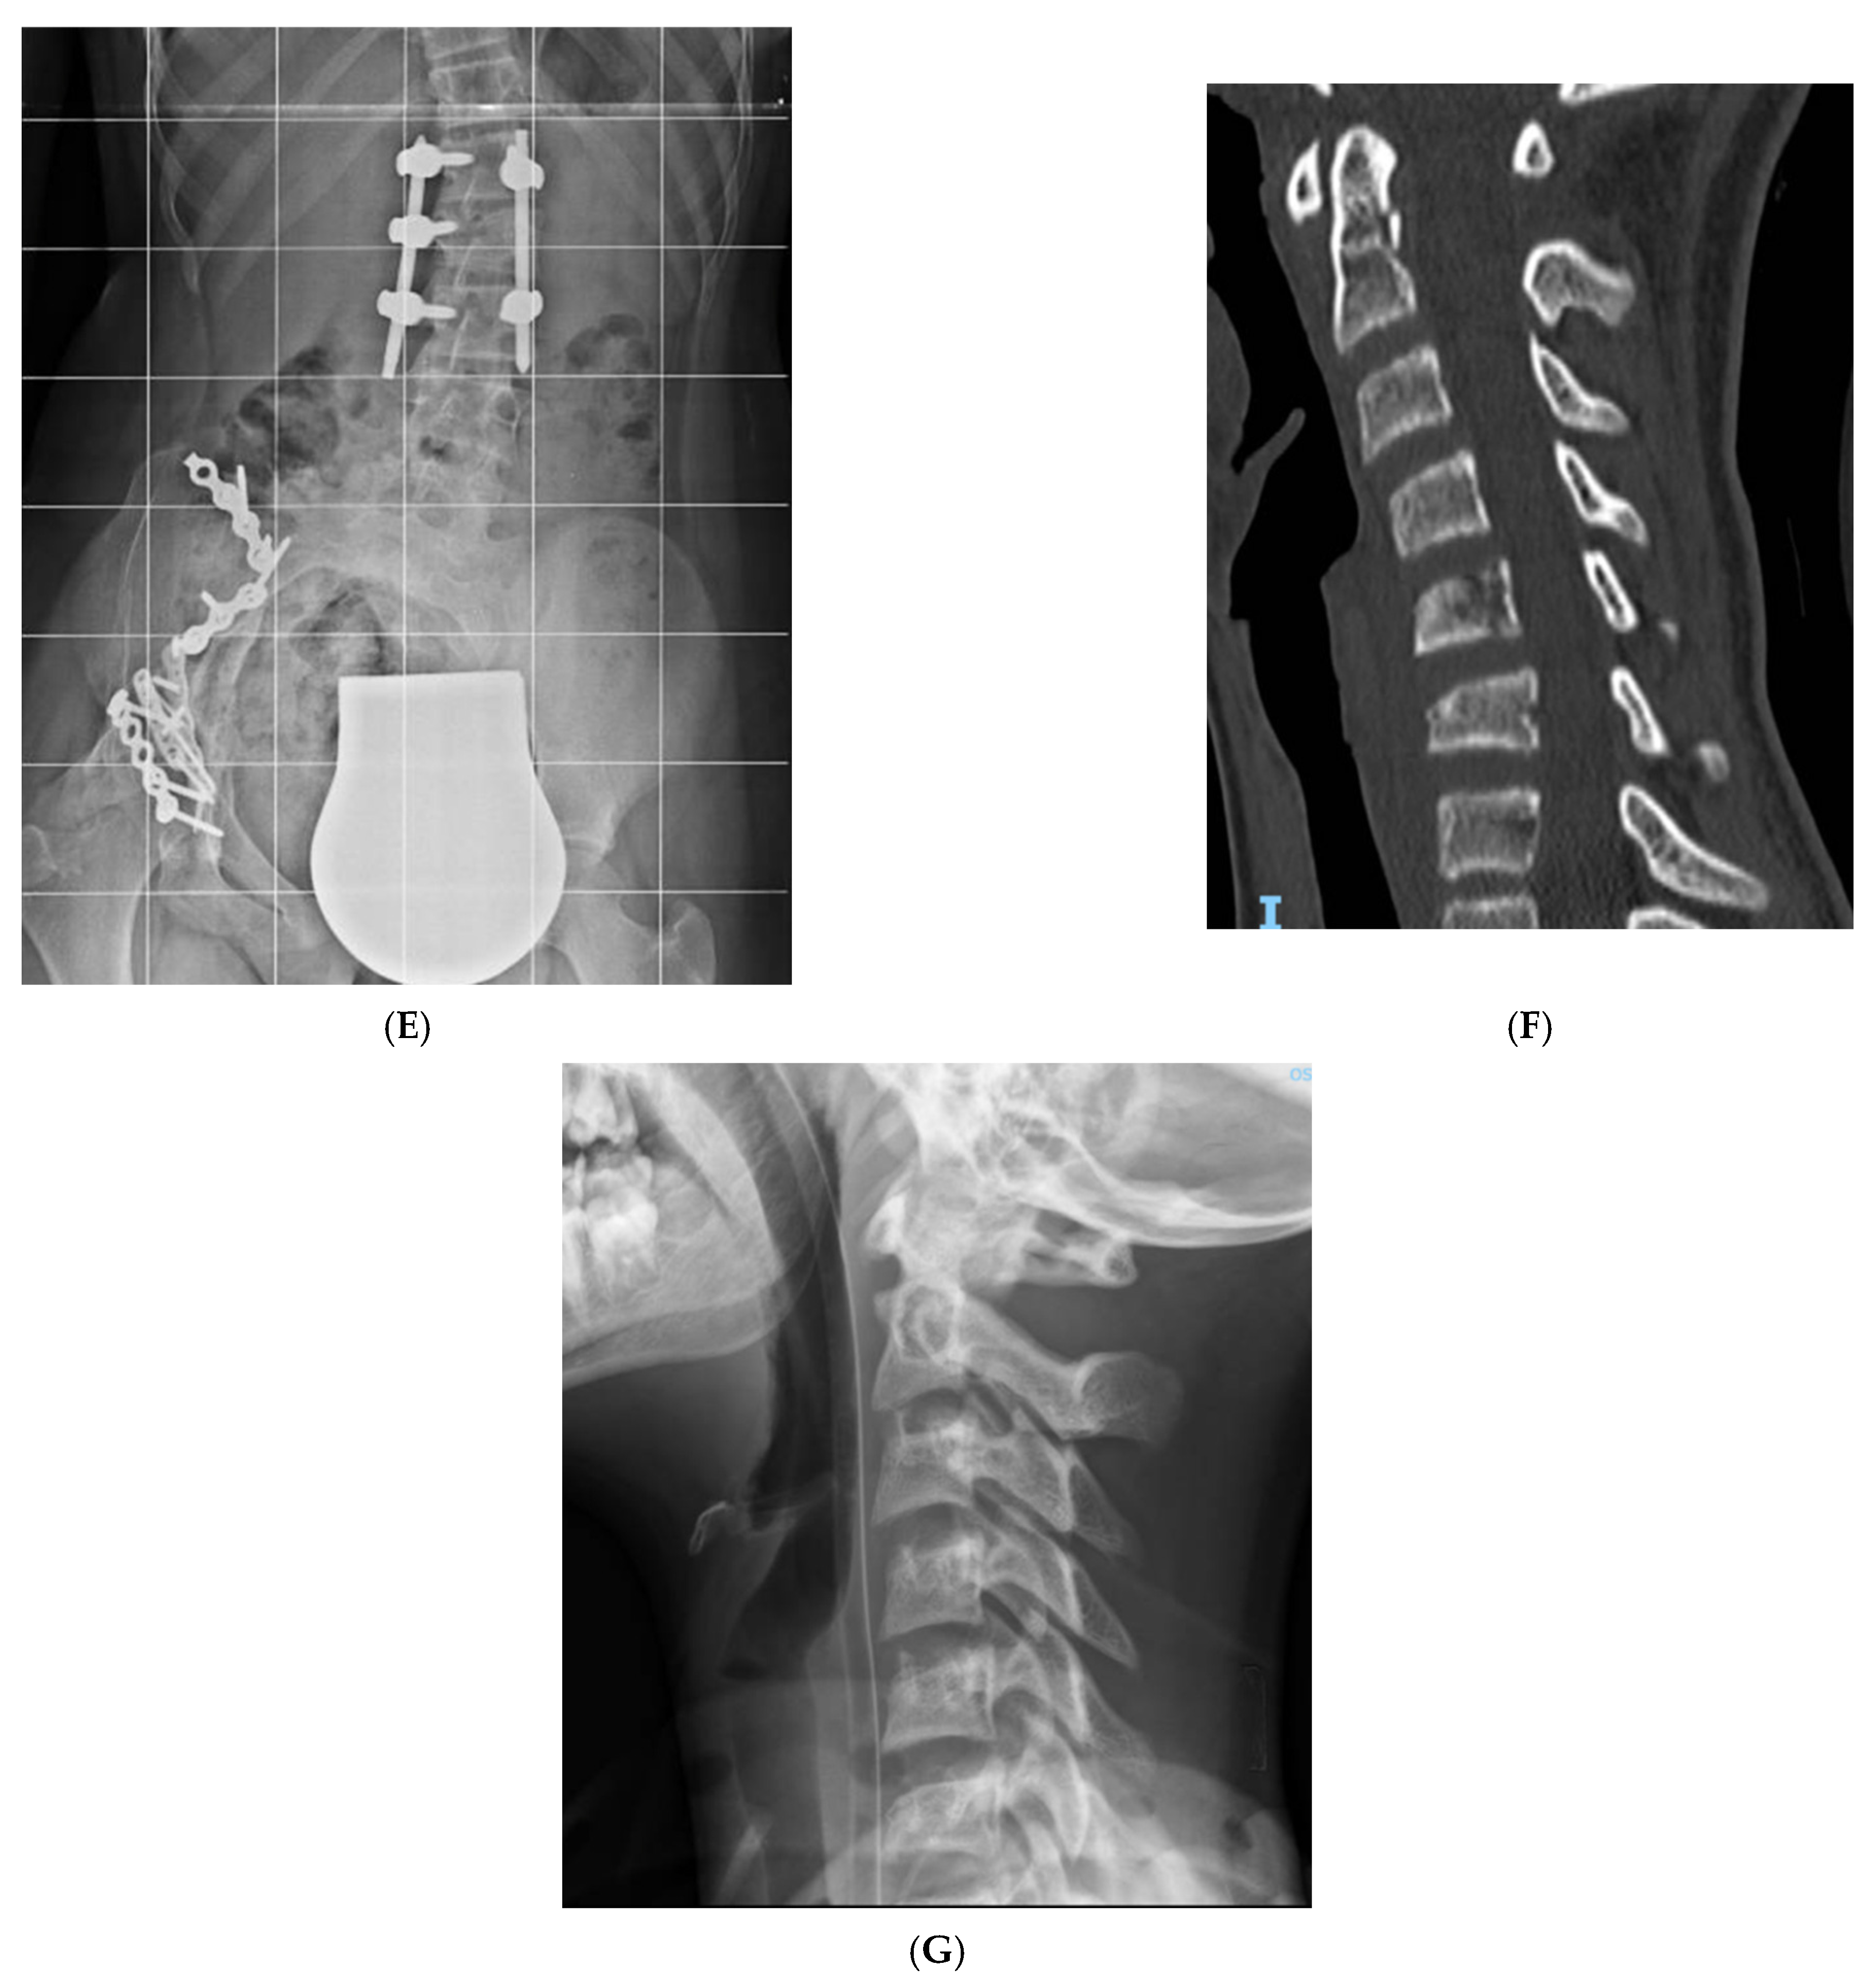

| 10 | G.A. | 16 y 6 m | M | L2 (A4), L5 (A4) | right orbital maxilla surface, right open tibia and fibula | L1 to S1 Percutaneous pedicle fixation | 40 | 6 months No deficit | |